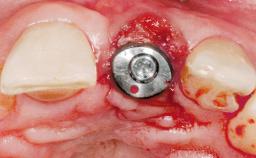

Immediate Placement of an Implant in a Maxillary Right Central Incisor Site

Type of Implants One-Piece|Reduced-Diameter

Attachment One-Piece|Reduced-Diameter

Bone Augmentation Horizontal|Simultaneous

Augmentation Materials Autogenous chips|Membrane

Placement Protocol Immediate implant placement

Tooth Site Maxillary incisor or canine

Socket Integrity Sufficient, with intact bone walls

Bone Volume Sufficient, with intact walls